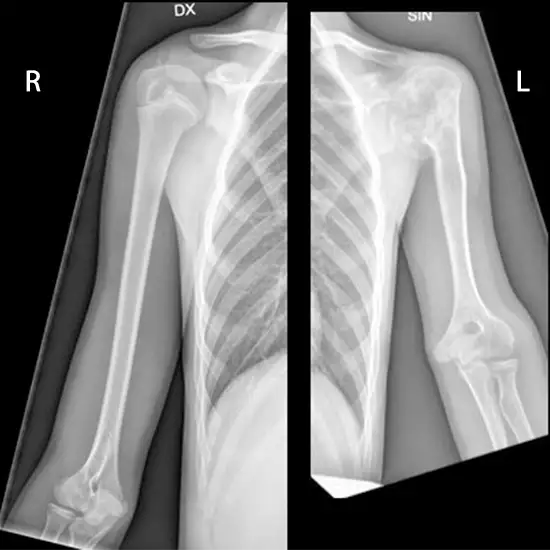

X-Ray Both Arm AP View

An arm X-ray is utilized to visualize the arm. It is advised in the case of arm symptoms such as discomfort, tenderness, or swelling. This technique detects fractures, infection, irregular growth, and dislocations in the arm's joints. It can also be used as a surgical guide and to monitor the healing process following surgery.

This view shows the elbow joint in its normal anatomical position. This makes it possible to check for suspected dislocations or fractures and find foreign bodies in the forearm.